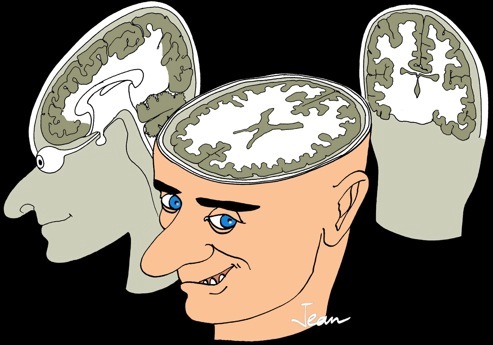

plan coronal

ou frontal

plan horizontal

plan sagittal

plan coronal

ou frontal

plan horizontal

plan sagittal